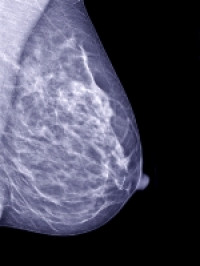

Breast tissue samples were taken from 40 women, with the results showing that all of the women had at least one paraben in their tissue. The research, published in the Journal of Applied Toxicology, was a collaborative study led by Dr Philippa Darbre, University of Reading and Mr Lester Barr, University Hospital of South Manchester.

The research team studied tissue samples from 40 women undergoing mastectomies between 2005 and 2008 for first primary breast cancer in England. In total, 160 samples were collected, four from each woman, covering serial locations from the axilla (nearest the armpit) to the sternum (breast bone). 99% of the tissue samples contained at least one paraben and 60% of the samples had five.

A number of studies since 1998 have raised concerns about the potential role of parabens in breast cancer as these chemicals possess oestrogenic properties and oestrogen is known to play a central role in the development, growth and progression of breast cancer. In particular, a link was proposed between the disproportionate incidence of breast cancer in the upper outer quadrant of the breast and oestrogenic chemicals in that region, maybe from local application of underarm cosmetic products.

There was a disproportionate incidence of breast cancer in the upper outer quadrant nearest the armpit and significantly higher levels of n-propylparaben were detected in the axilla region, closest to the armpit, than in the mid or medial regions. The other four parabens were equally distributed across all parts of the breast.